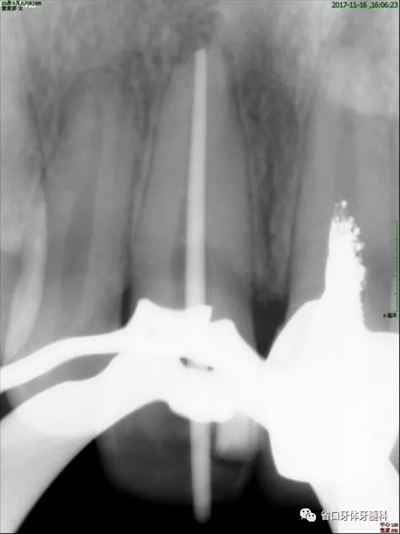

2周后復(fù)診:封藥存,患牙無(wú)不適,叩痛-,齦無(wú)紅腫。去封藥,清理根管,試主尖到位,沖洗、干燥,熱牙膠充填至釉牙骨質(zhì)界下2mm,照片顯示恰充。

圖4 試尖片